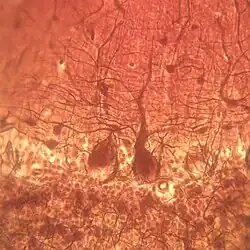

Клетка Пуркинье

Клетки Пуркинье — это ГАМК-эргические (передающие сигнал при помощи нейромедиатора гамма-аминомасляной кислоты) тормозные нейроны, единственные «выходные» нейроны коры мозжечка. Длина аксона у мышей — 2 миллиметра, у крыс — 3 миллиметра. Толщина дендритов 2—5 мкм — толстые ветви, 0,5—1 мкм — тонкие. Тело клетки Пуркинье имеет грушевидную форму, от которой отходит множество дендритов, обильно разветвляющихся в плоскости, строго перпендикулярной извилинам мозжечка, и образующих множество (до двухсот тысяч[1]) синапсов с пересекающими слои таких деревьев параллельными волокнами — расположенными вдоль поверхности извилин аксонами гранулярных клеток мозжечка. Высокоразвитое дендритное древо клетки Пуркинье поддерживает своими отростками глиоцит Бергманна — «специализированный астроцит». Длинный аксон (причём не обладающий аксонным холмиком), который берёт своё начало от расположенного в глубине коры мозжечка основания клетки, направляется через белое вещество к ядрам мозжечка, образуя синапсы с их нейронами, а также к вестибулярным ядрам[2].